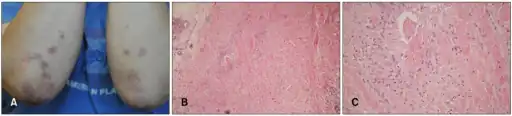

| Micrograph of a rheumatoid nodule, showing the characteristic palisading granuloma with a core consisting of necrotic collagen and fibrin. H&E stain. | |

Histological examination of nodules shows that they consist of a shell of fibrous tissue surrounding a center of fibrinoid necrosis.[13] Pea-sized nodules have one centre. Larger nodules tend to be multilocular, with many separate shells or with connections between the necrotic centers. Individual necrotic centers may contain a cleft or several centers of necrosis may all open on to a large bursal pocket containing synovial fluid.

The boundary between the necrotic center and the outer fibrous shell is made up of the characteristic feature of the nodule, which is known as a cellular palisade. The palisade is a densely packed layer of macrophages and fibroblasts which tend to be arranged radially, like the seeds of a kiwifruit or fig.[13] Further out into the fibrous shell there is a zone that contains T cells and plasma cells in association with blood vessels.[14] The histology of pulmonary nodules are similar to that of subcutaneous nodules, with central necrosis surrounded by palisading macrophages and inflammatory infiltrate.[5]

Differential diagnosis of rheumatoid nodules can be classified from localization, depth pathology, age of onset, persistence, rheumatoid factor, concomitant joint disease, and bone erosions. Diagnosis is typically determined clinically by a rheumatologist.[5] Rheumatoid arthritis associated rheumatoid nodules are typically subcutaneous and occur at extensor sites. The onset typically starts in adulthood and presents with rheumatoid factors and bone erosions, and concomitant joint diseases. The pathology is characterized by central necrosis, palisading mononuclear cells, and perivascular lymphocytic infiltrations.[14]